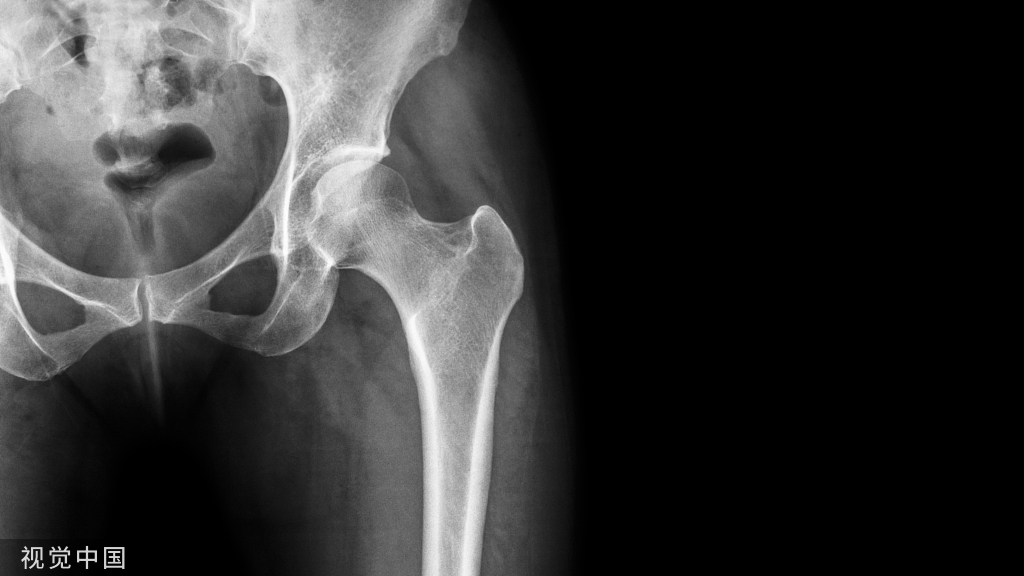

在过去的50年里,髋关节置换术已经成为一种常见的手术方式,其中半关节置换术和全髋关节置换术是最常用的髋关节置换术。此外,植入物和手术方法都在稳步改进,不同的植入物被用于治疗髋关节置换中的不同情况,从表面植入物到巨型假体。半关节置换术包括用人工假体替换天然股骨头和股骨颈,保留天然髋臼不受影响。在全髋关节置换术中,股骨和髋臼关节表面都被人工假体取代。

X线片是评估髋关节置换术和确定术后并发症的一种标准的基本检查。CT扫描或磁共振成像相比,X片不仅简单、成本更低、受伪影影响更小,而且还提供更高的图像分辨率和更少的时间。放射科医生和整形外科医生可以根据患者以前的手术记录或术后系列图像很容易地区分这两种假体。

然而,每次遇到术后图像时检索手术记录或术后连续图像可能会导致图像解释过程的复杂性和复杂性。此外,可能没有在另一家机构进行手术的某些病例的记录,或者它们可能已因过时而被丢弃。这迫使读者只能依靠诊断图像来区分。由于两种髋关节假体的外形相似,在X线片上,假体由一个球状杯和环绕髋关节的股骨柄组成,因此很难区分它们。